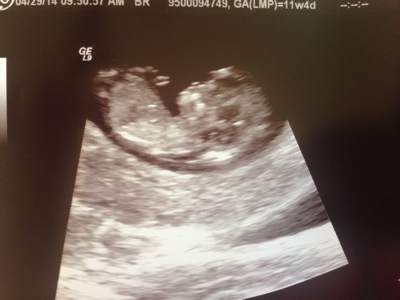

Hello! I'm new to this forum but I'd love to hear what you guess from our 12 week 0 day ultrasound. I really appreciate you taking the time to guess. Skull and Nub guesses would be great! Thanks so much!

Attachment 18910